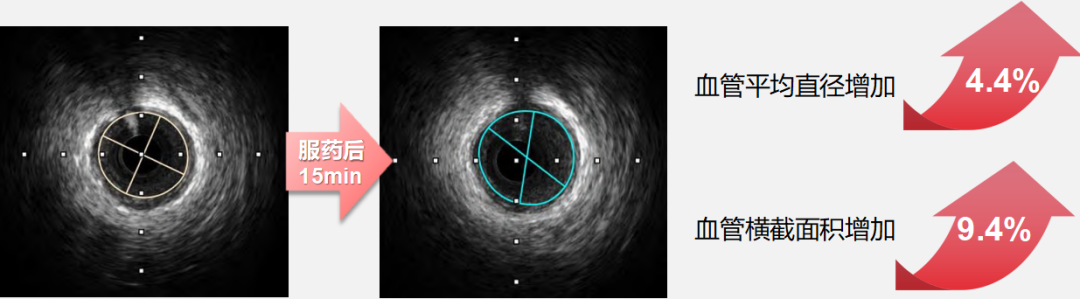

●而速效救心丸展现出 “精准化” 的血管调控特征:对直径 2.00-2.75mm 的细小冠状动脉扩张作用更突出,服药后15 分钟该直径区间血管横截面积面积扩张百分比最高可达 8.58%(如下图),且扩张过程中患者血压、心率等血流动力学指标无显著波动。